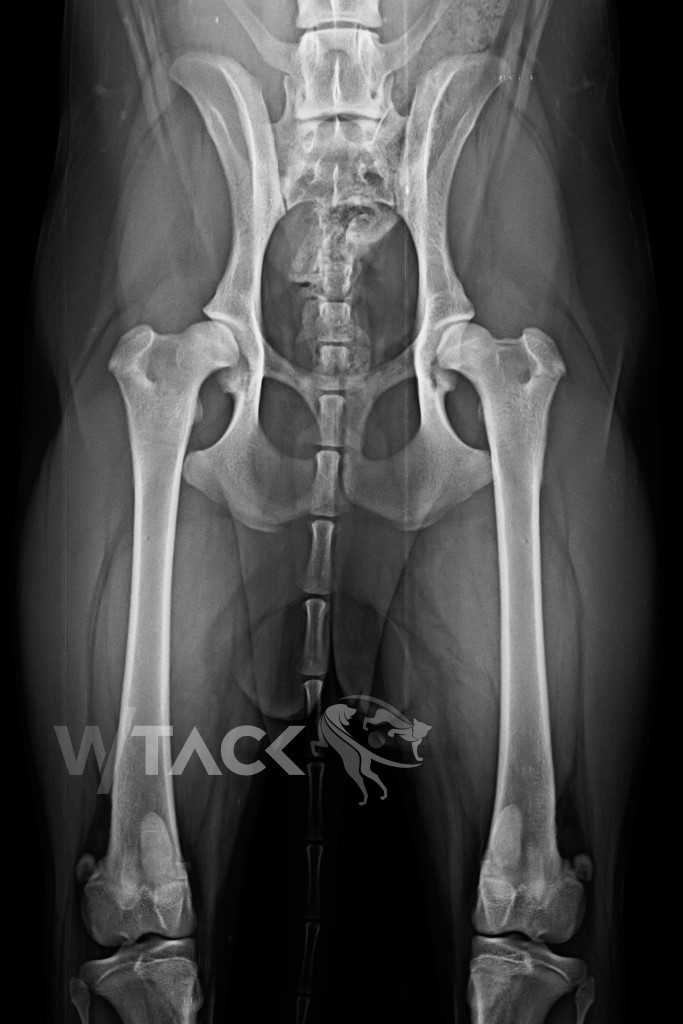

Bild 01 – präoperativer Zustand, beiderseits HD